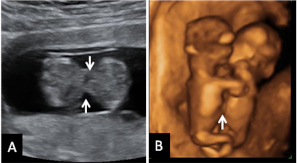

Vemos en esta ecografía en dos dimensiones de un feto de 12 semanas. Si nos fijamos en la flecha, el tubérculo genital apunta hacia delante, lo que hace muy probable que el feto sea de sexo varón.